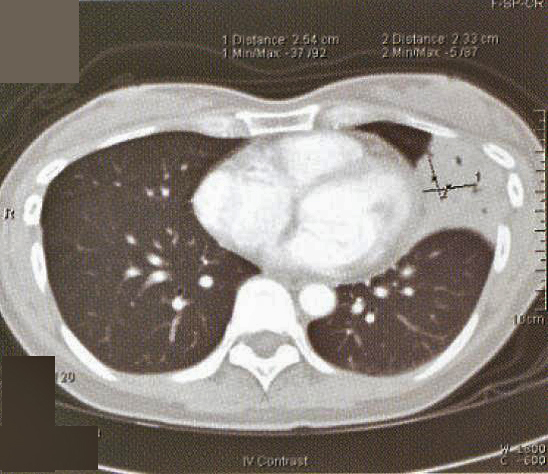

Fig. 1: CXR taken at presentation (a) and 17 days later (b). Left mid zone opacity remained unchanged despite a course of Azithromycin Blood tests revealed normal CBP, ESR & routine biochemistry. Antibodies for HIV 1 & 2 were negative. Thyroid function was normal but thyroid peroxidase antibody was elevated at 81.7 IV/ml (normal <12). CT thorax showed an area of segmental consolidation in the lingular segment of left upper lobe (fig. 2a), with no abnormality detected in other parts of the lungs, mediastinum or body structures. Bronchoscopy revealed nothing abnormal and bronchial washings grew alpha streptococcus but were negative for AFB smear, M tuberculosis DNA or malignant cells. She developed a cough after the bronchoscopy and responded to a course of levofloxacin.

Fig. 1: CXR taken at presentation (a) and 17 days later (b). Left mid zone opacity remained unchanged despite a course of Azithromycin Blood tests revealed normal CBP, ESR & routine biochemistry. Antibodies for HIV 1 & 2 were negative. Thyroid function was normal but thyroid peroxidase antibody was elevated at 81.7 IV/ml (normal <12). CT thorax showed an area of segmental consolidation in the lingular segment of left upper lobe (fig. 2a), with no abnormality detected in other parts of the lungs, mediastinum or body structures. Bronchoscopy revealed nothing abnormal and bronchial washings grew alpha streptococcus but were negative for AFB smear, M tuberculosis DNA or malignant cells. She developed a cough after the bronchoscopy and responded to a course of levofloxacin.

She was treated with chemotherapy – 3-weekly regime of cyclophosphamide, adriamycin, vincristine & prednisolone (CHOP) – and tolerated the treatment well. A CT thorax was performed after 3 cycles of chemotherapy showed a slight reduction in the area of consolidation (fig. 2b).

The radiographic changes of pulmonary MALToma are non-specific. CXR and High resolution CT thorax usually show multi-focal, ill-defined nodules containing air bronchograms or focal lobar consolidation similar to what is seen in this patient. Mediastinal lymphadenopathy and pleural changes are rare. These features are similar to those seen in bronchoalveolar cell carcinoma or bronchiolitis obliterans with organizing pneumonia (3). The possibility of MALToma should be considered in patients with non-resolving pneumonia, especially if there is an absence of prominent systemic or respiratory symptoms.